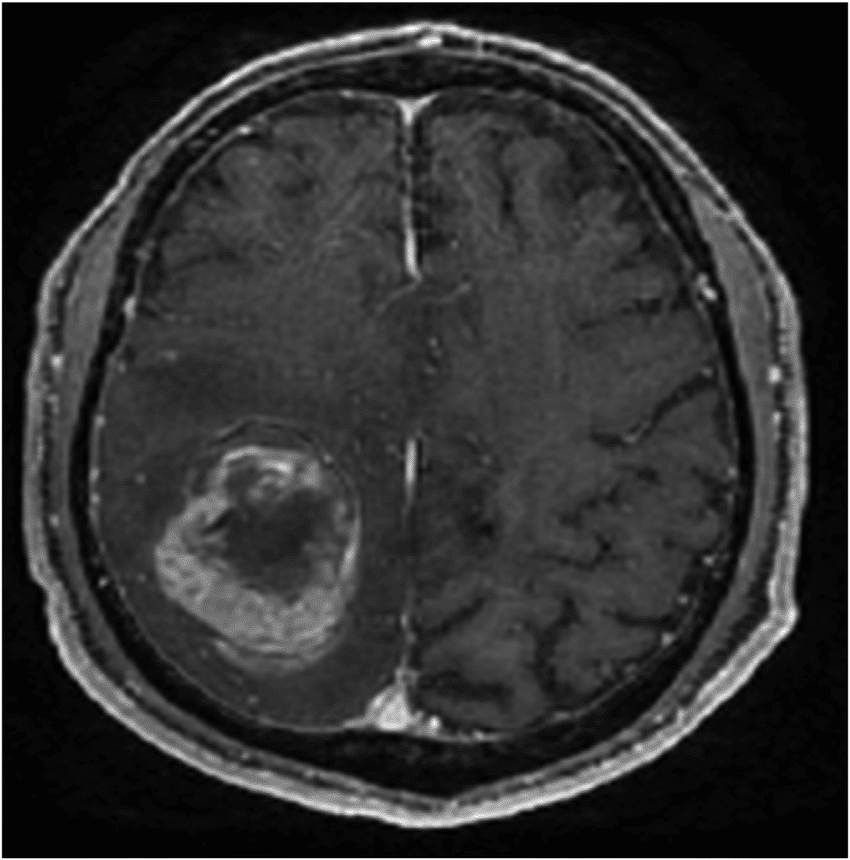

Une étude scientifique sur les cancers du cerveau a permis de découvrir que certains cancers du cerveau contiennent des cellules souches qui sont à l’origine de tous les types de cellules cancéreuses dans la tumeur. Ce projet de recherche, mené par les Universités de McGill et Calgary, ouvre la voie à de nouveaux traitements du cancer du cerveau, plus spécifiquement, le glioblastome.

Le glioblastome est un cancer du cerveau très dangereux, car il résiste aux traitements. Par exemple, la chimiothérapie et la radiothérapie pratiquées sur un patient peuvent atténuer le cancer, mais au bout d’environ sept mois, celui-ci revient. La raison de son retour a longtemps intrigué les neurologues et grâce au Dr Kevin Petrecca, neurochirurgien et chercheur dans le domaine du cancer du cerveau à Neuro, un institut et hôpital neurologique de Montréal à McGill, qui a conduit la recherche, son équipe et lui ont réussi à produire un portrait précis de ce cancer.

Il faut savoir qu’un glioblastome est une tumeur qui contient quatre types de cellules : les trois premiers types, bien connus des neurologues, et un quatrième, les cellules souches, qui étaient encore inconnues. Après avoir détecté pour la première fois les cellules souches de glioblastome (CSG) progénitrice (qui assurent une descendance), Kevin Petrecca et son équipe se sont intéressés à en connaître davantage sur ces dernières, car ils étaient convaincus qu’elles étaient à l’origine de tous les types de cellules présents dans la tumeur.

Grâce à plusieurs recherches, ils ont découvert que les cellules souches de glioblastome ont tendance à se multiplier beaucoup plus vite que les cellules de cancer habituelles. Cela explique la résistance des tumeurs cérébrales aux traitements: chaque traitement cible habituellement un seul type de cellule, et même si on attaquait les trois premiers types, on ignorait qu’il y avait toujours des cellules souches qui pouvaient produire de nouvelles cellules cancéreuses pour remplacer celles qui avaient été tuées.